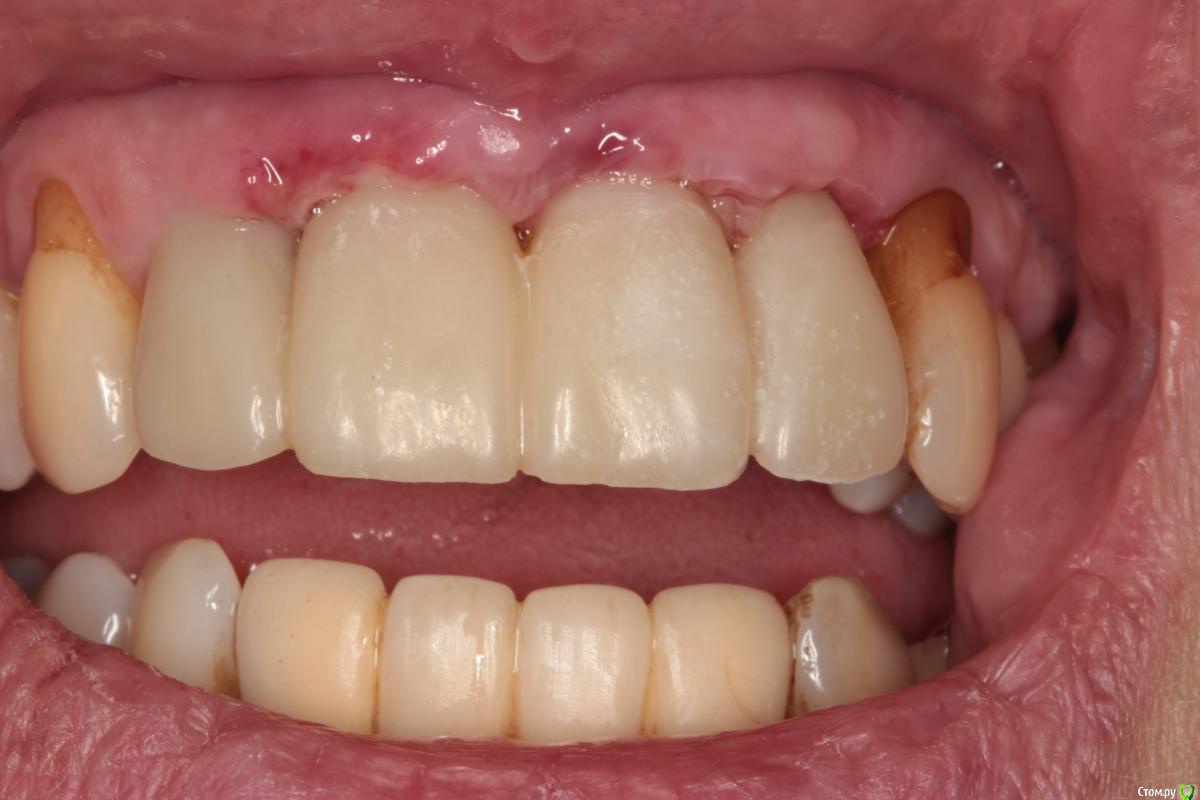

Abuk Опубликовано 27 ноября, 2015 Поделиться Опубликовано 27 ноября, 2015 (изменено) 1.bmp2.bmp3.bmp4.bmpЛечение.Альгинатные слепки,восковая моделировка.Удаление зубов и имплантата,удаление грануляций.Установка имплантатов,заполнение лунок графтом.сст,Времяхи по ключу. Изменено 27 ноября, 2015 пользователем Abuk 13 Ссылка на комментарий

Карен Аванесов Опубликовано 30 ноября, 2015 Поделиться Опубликовано 30 ноября, 2015 Конечный результат не забудьте показать. Ссылка на комментарий